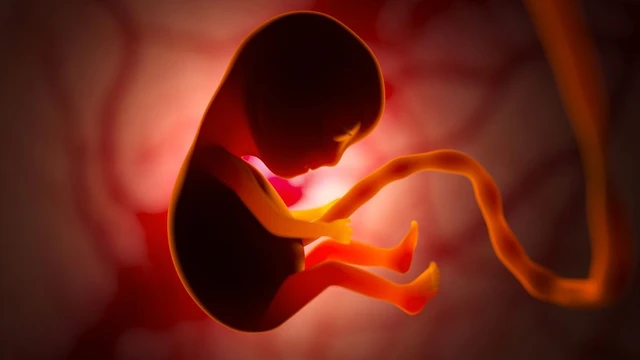

Thai bị thiếu máu là một trong những tình trạng y khoa đáng lo ngại trong thai kỳ, có thể dẫn đến nhiều biến chứng nghiêm trọng như suy tim thai, phù thai, thậm chí là đe dọa tính mạng của thai nhi nếu không được phát hiện và can thiệp kịp thời.